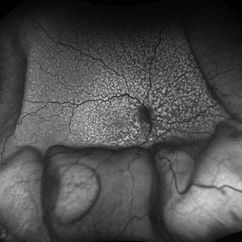

Choroidal Metastasis With Orange Pigment in a Patient With Endometrial Carcinoma

Choroidal Metastasis With Orange Pigment in a Patient With Endometrial Carcinoma

Aug 8 2024 by Guilherme Sturzeneker, MD, MSc

Ultra-widefield fundus photograph and autofluorescence of a 62-year-old woman with endometrial cancer, denoting choroidal metastasis with unusual orange pigment. This presentation is a reminder that the development of orange pigment is not pathognomonic for choroidal melanoma, as it may be seen in other lesions such as carcinoma metastasis.

Photographer: Andrea Almeida

Imaging device: Optos Silverstone

Condition/keywords: choroidal metastasis, metastatic cancer, orange pigment